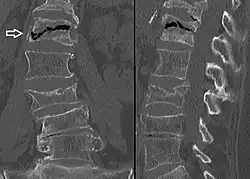

X-ray images of avascular necrosis in the early stages usually appear normal. In later stages it appears relatively more radio-opaque due to the nearby living bone becoming resorbed secondary to reactive hyperemia.[2] The necrotic bone itself does not show increased radiographic opacity, as dead bone cannot undergo bone resorption which is carried out by living osteoclasts.[2] Late radiographic signs also include a radiolucency area following the collapse of subchondral bone (crescent sign) and ringed regions of radiodensity resulting from saponification and calcification of marrow fat following medullary infarcts.

The intravertebral vacuum cleft sign (at white arrow) is a sign of avascular necrosis. Avascular necrosis of a vertebral body after a vertebral compression fracture is called Kümmel's disease.[20] -